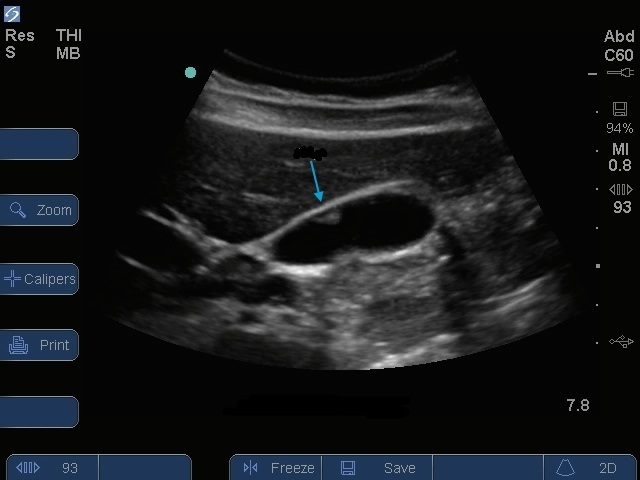

Bild: Gallenblasenpolyp

Blauer Pfeil: Polyp